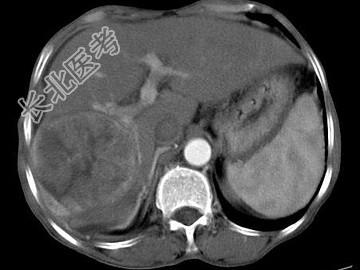

- 单项选择题女,40岁, 有口服避孕药史,肝区疼痛、腹部包块, AFP阴性,CT扫描如图, 最可能的诊断是

A、肝细胞腺瘤

B、肝再生结节

C、结节性肝癌

D、肝右叶巨块型肝癌

E、肝黄色肉芽肿